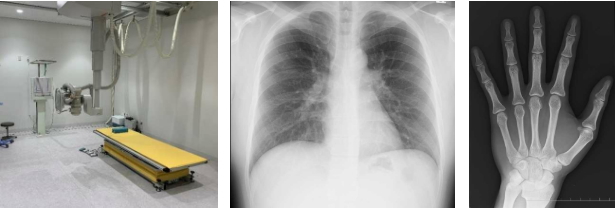

○ 一般撮影

レントゲンとも呼び、X 線を用いて肺や骨など様々な部位を撮影し画像にします。

フィルムレス化により撮影した画像が診察室ですぐ確認できるようになり、パソコン上で撮影した画像を見ることができます。

検査を行う際に服を脱ぐ場合や、下着やアクセサリー類・金属類などを外していただく場合があります。

ご協力よろしくお願いいたします。

○ 骨密度測定

骨の量や密度を測定する検査です。当院では DXA 法(二重エネルギーX 線吸収法)を用いて腰椎と股関節の画像から骨密度を測定しています。

検査時間は 5分ほどかかりますが信頼度が高い検査です。